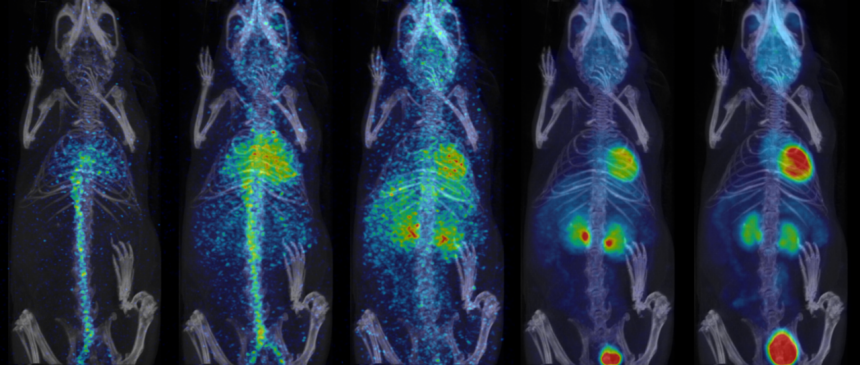

- Fully automated PET/CT stitched protocol, including attenuation correction (AC) map for rats up to 250 mm in length

Fast extended PET/CT imaging for full rat body coverage. Image Credit: Bruker BioSpin Group